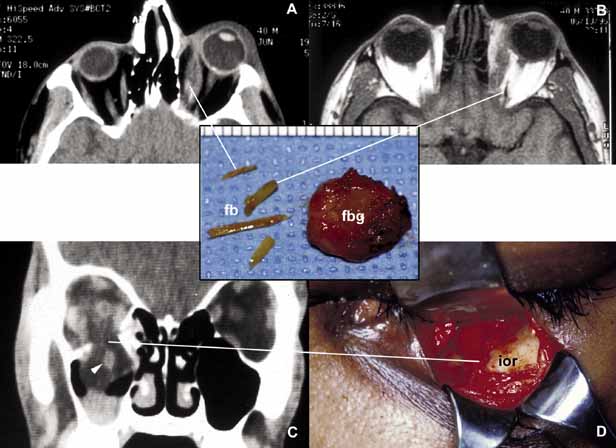

ANOPHTHALMOS/MICROPHTHALMOS When the globe is abnormally developed, microphthalmos, congenital cystic eye, and extremely rarely, anophthalmos occur. Microphthalmos usually occurs as a unilateral condition and in approximately 10% of cases it is associated with other craniofacial malformations including agenesis of the corpus callosum, polymicrogyria, and mid-line arachnoidal cysts. Microphthalmos may be seen as a part of several genetically determined neuronal migration disorders such as Walker-Warburg syndrome, Aicardi syndrome, and Fukuyama congential muscular dystrophy.9,10 In cases of microphthalmos and anophthalmos the orbit may be well formed but does not develop to a full adult volume. The mechanism by which the presence of the globe effects the growth of the orbit is not well understood. Microphthalmos may be associated with a colobomatous cyst as a result of the abnormal closure of the embryonic optic fissure leading to the prolapse of neuroectodermal tissues into the orbit (Fig. 1) This cystic structure may increase rapidly in size to overshadow the abnormal globe and may be confused with a neoplasm. When cystic lesions in the orbit are suspected imaging studies should be performed not only to look for other intracranial abnormalities but also to establish the possible connection of the cyst to the colobomatous globe versus to abnormally formed meninges.11 Macrophthalmos (buphthalmos) may also rarely develop as a congenital anomaly in patients with Sturge-Weber syndrome and rarely in neurofibromatosis type I. ORBITO-CRANIAL MALDEVELOPMENTS Cephalocele results from the extension of maldeveloped CNS tissues including meninges (meningocele), brain parenchyma (encephalocele), and the combination of the two (meningoencephalocele) into the orbital cavity.12,13 Intraorbital cephaloceles may develop anteriorly at the suture lines of orbital bones or posteriorly extending into the orbit from orbital fissures and the optic canal. Depending on the combination of these herniations they contain brain and/or meningeal tissues (Fig. 1). Aberrant fibroglial tissue has also been described in the orbit.14 Hamartoma is a tumor-like proliferation of tissues that normally exist at a given body location. The best examples of orbital hamartomas are the vascular hamartomatous lesions that are composed of vascular elements including capillary endothelial cells, distended or collapsed cavernous blood and lymph vessels, tortuous arterial and venous channels with or without anastomoses, etc. Other examples of hamartomatous orbital tumors include neurofibroma and lipomatous hamartoma.15 Choristoma, however, is a tumor-like proliferation of tissues that are not normally present at a given body location. The most commonly encountered example of orbital choristoma is a dermoid.16 Dermoids that present with many varieties result from the entrapment of epithelial structures at the site of closure of fetal fissures. Superficial dermoid cysts occur primarily subcutaneously anterior to orbital septum or within the anterior orbit. If the cyst wall is made of epidermis without dermal tissues, it is classified as an epidermoid cyst. These lesions are occasionally lined by conjunctival or pseudostratified respiratory epithelium.17 The superficial lesions must be distinguished from deep orbital dermoids that are usually rounded, encapsulated tumors filled with fatty materials, keratin, and dermal structures such as hair particles. Histopathologically the dermoid wall is lined by keratizing squamous epithelium with dermal appendices including hair follicles and sebaceous and eccrine glands.18 Most of the dermoids are well outlined by ultrasonography because of their anterior location thus making CT or MRI rarely necessary.19 If the dermoid is unusually large or located at the frontal zygomatic suture, CT is necessary to document the relationship of the lesion to the bone before surgical intervention. Rarely, dermoids at the fronto-zygomatic suture may develop dumbbell-shaped lesions partially within the orbit and partially extending into the temporal fossa.20,21 Unusually large superior orbital dermoids particularly those that leak and create granulomatous reaction within adjacent soft tissues may erode the bone and extend into the frontal sinus or the cranium (Fig. 2). ORBITAL TERATOMA Teratoma is a germ-cell tumor that contains tissues derived from endoderm, ectoderm, and mesoderm22 (Fig. 1). Therefore, these lesions may contain skin, bowel, lung, brain, thyroid, cartilage, and bone tissues. Most teratomas develop unilaterally and in girls. A majority of these congenital tumors are benign. Occasional reports have documented malignant transformation within orbitocranial teratomas.23 However, these benign tumors continue to grow after birth because of the collection of secretions from different tissues into the partially cystic spaces of the tumor. Some teratomas create massive proptosis and most can only be treated by exenteration. However, some of these lesions have recently been reported to be removed surgically with preservation of the globe and other vital orbital structures. TRAUMA Mechanical Injury Orbital injuries result from the absorption of kinetic energy that occurs whenever the orbital tissues contact an object moving at a different speed.25 The orbital rim is capable of absorbing a considerable amount of kinetic energy without being fractured. Yet, a variety of impact forces striking the orbit may result in fractures in different areas.26 The absorption of the kinetic energy by an orbital bone may lead to contusion and/or laceration of the skin and superficial soft tissues, local deformation of the adjacent structures, globe, orbital soft tissues and bones and increases pressure in the orbital cavity. A common end result of an orbital impact is the fracture of the floor and/or the medial wall (lamina papyracea)27 (Fig. 3). Fractures of other orbital bones occur less often. Foreign bodies may be introduced into the orbit at the time of injury and may cause secondary problems depending on the nature and the location of the foreign body.28 Some foreign bodies such as copper may cause tissue necrosis and degeneration (chalcosis), and others particularly organic matter, may carry organisms such as bacteria and fungi into the orbital tissues and cause secondary infections29 (Fig. 3). Once the fracture of an orbital bone occurs, it may produce sharp edges to lacerate adjacent soft tissue structures including the globe, optic nerve, other nerves, muscles, and vessels.30 Depending on the damage of the particular tissue, functional deficit results. Another issue to deal with in an injured orbit is the development of hematoma, hematic cyst, and cholesteotoma. Hemorrhage in the orbit may occur spontaneously without any physical exertion in healthy individuals. Although terminology is not very strict, hematoma usually refers to a localized collection of blood within orbital soft tissues that develops secondary to trauma. When the blood collection within the orbit becomes organized and surrounded by a thin pseudocapsule, it is known as a hematic cyst31 (Fig. 4). If the hemorrhage develops within an existing lymphatic or vascular tumor, these lesions are known as blood cysts or “chocolate” cysts.32 Hematic cyst consists of a localized collection of blood surrounded by a nonepithelium-lined thin fibrous capsule.33 These lesions usually develop within 1 to 2 weeks of orbital trauma but chronic cases may occur up to 20 years after orbital injury.34,35 They may reach to a size causing proptosis, extraocular motility disturbance, compression on the globe and optic nerve, that can easily be detected with ultrasonography, CT, or MRI. Hematic cysts may develop within the muscle cone or in the extraconal orbital locations.33–36 These cysts are lined by fibrovascular tissue at the periphery and contain degenerated erythrocytes, protein debris, and cholesterol crystals. In many instances the thin nonepithelial lining is adherent to the adjacent structures with fibrous tissue. Cholesteatoma is another cystic lesion that is confined within a “pseudowall” without an epithelial lining.37 Cholesteotomas are usually located in the superior lateral orbit within the lacrimal gland fossa. Imaging studies may show a cystic, semi-cystic, or a solid lesion within the diploe of the bone or within the orbital soft tissues, with or without erosion of the adjacent bone.38 Histopathologically the lesion is composed of cholesterol clefts, hemosiderin, and hematoidin granules, other blood breakdown products and fibrin surrounded by a mixed lymphohistiocytic infiltrate and multinucleated foreign body giant cells.39 On imaging studies these lesions appear as unilocular rounded masses with destruction of the adjacent frontal and zygomatic bones. Although bone involvement in general implies malignancy, the sclerosing character of the bony destruction in choleosteoma, which is best seen in bone window images, favors a benign lesion. Although bone destruction also makes one think along the lines of metastatic tumors, one should also consider benign lesions such as brown tumor, aneurysmal bone cyst, and ruptured dermoid. Multiple cuts of the frontal bone should be examined to rule out the possibility of intracranial extension. Osteomyelitis of the orbital bones evolving as a complication of paranasal sinusitis is another entity that should be considered in the differential diagnosis of cholesteotoma. In osteomyelitis the bone infection extends into the periosteal space and beyond. Precise delineation of the lesion can be performed with CT and MRI particularly in combination with bone SPECT, a sensitive technique used to detect osteomyelitis within cranial and orbital bones.40 Mucocele Although a commonly encountered space occupying lesion in the orbit, mucocele is technically not a neoplasm. It is a cystic cavity lined by pseudostratified respiratory epithelium prolapsing into the orbit from a paranasal sinus, most commonly the frontal followed by the ethmoidal sinus (Fig. 5). Primary mucoceles develop as a result of an inflammatory obstruction of the ostium of the paranasal sinuses. Secondary mucoceles, however, are most commonly seen after orbital trauma and surgery; they may also develop secondary to neoplasms of paranasal sinuses and nasopharynx. If there is a superimposed infection, the lesion is referred to as pyocele. The mucocele develops as a well delineated cystic structure originating from a paranasal sinus. Depending on the location, it may compress orbital structures including extraocular muscles, optic nerve, and the globe.41 Clinical presentation of the mucocele is usually with globe displacement and/or proptosis, extraocular motility deficiency, particularly in the direction of the sinus extension into the orbit, and other compressive symptoms.42 The crepitant or calcified hard wall of the mucocele may be palpated underneath the superior or medial orbital rim. Mucoceles in general, are rare in children, however, a unique variant, ethmoidal mucopyocele, is known to occur in the medial canthal area, with lateral displacement of the globe. On CT, mucoceles present as hypointense, expanding masses originating from the paranasal sinuses. Early in their development these lesions are small, mucous-containing cysts. Later they are characterized by crescent-shaped and thinned remodeling of the bony walls of the orbit and sinuses.43 On MRI, mucocele presents with different appearances depending on the amount of free water within its luminal contents. When the intraluminal mucous becomes inspissated, the signal intensity in both T1 and T2 images decrease, getting closer to normal air content of the sinus.44 Treatment of mucocele is surgical excision. Other injuries with toxic chemicals and radiation are known to damage orbital tissues.45–47 VASCULAR MALFORMATIONS Arteriovenous Fistula Orbital arteriovenous (AV) fistulas are established as a result of abnormal flow between the arteries and veins. These lesions can be divided into three basic types: carotid cavernous, dural and orbital AV fistulas. Carotid cavernous fistula is usually traumatic but may also develop secondary to a rupture of an aneurysm particularly in elderly atherosclerotic patients. These fistulas commonly develop between an intracavernous segment of internal carotid artery and cavernous sinus and shunt arterial blood into superior ophthalmic vein.48 Dural cavernous fistulas, however, develop between small meningeal branches of internal/external carotid artery and the cavernous sinus. These small vessels that have thin walls that may rupture spontaneously particularly in hypertensive individuals, secondary to minor trauma and maintain a low blood flow. Orbital AV fistulas usually develop secondary to traumatic rupture of the ethmoidal artery into the orbital venous system. This type of fistula maintains a low blood flow. Clinical findings of AV fistulas include rapidly developing proptosis, edema of the conjunctiva and eyelids, dilatation and tortuosity of the conjunctival and episcleral vessels, and secondary glaucoma. Most of these cases are diagnosed with imaging procedures including CT, MRI, angiography, color Doppler ultrasonography, and catheterized angiography.49 Current treatment of these lesions is embolization via catherization.50 Morphologic data are limited to autopsy material because most patients with AV fistulas do not undergo biopsy procedure. These lesions show irregular, malformed arteries and veins with abnormal elastic and muscular layers and secondary endothelial cell proliferation. Approximately half of the low shunt fistulas close spontaneously;51 therefore, it is best to follow-up some of these patients conservatively if they do not have severe symptoms. Orbital Varix Orbital varix is a rare vascular lesion with questionable histopathogenesis. The absence of valves in the orbital venous system and the weakening of venous wall may lead to pooling and stasis of blood resulting in distention of the venous channel with thrombosis. In gross appearance, the varix is a distended vein containing a canalized or uncanalized thrombus.52,53 Histopathologically varix consist of irregular vascular channels lined by endothelial cells. In chronic lesions, the blood vessel walls irregularly thicken with fibrosis and deposits of chronic inflammatory cells mixed with deposits of calcium and hemosiderin pigment are seen. Orbital varices are divided into primary and secondary types. The primary orbital varix is confined to the orbit as an isolated lesion without any connection to other A-V malformations. The secondary orbital varix, however, develops as an extension of an intracranial AV malformation that shunts blood to the orbital venous system causing the venous channels to distend secondarily.54 Management of orbital varix consists of total surgical excision when possible and/or endovascular embolization. | |||||||||||||||||||||||||||||||||||||||

Orbital cellulitis may also be caused by different types of foreign bodies including organic and nonorganic matter and nonautogenous surgical implants.28 Inorganic foreign materials, such as metal and glass, are usually well-tolerated and do not cause infection unless they significantly distort the orbital anatomy with exposure to periorbital sinuses and nasal cavity. Organic foreign bodies such as wood, vegetable fibers, etc., however, trigger significant foreign body reaction and sometimes suppurative inflammation.These should be documented by CT and/or MRI and surgically removed29 (Fig. 3). Today many nonautogenous materials are used in ocular and orbital reconstruction, including porous implants, mesh materials, polymeric silicone plates, sponges for scleral buckling procedures and reservoirs of drainage valves for glaucoma. Implants and repair blocks made of porous materials may lead to acute infection when they erode through sinus or conjunctival epithelium. Whenever there is a foreign body, noncaseating granulomatous reaction with multinucleated giant cells is identified, adjacent to the foreign material; secondary acute inflammation may be superimposed. In penetrating injuries the nature of the foreign body is an important factor. An exception to suppurative soft tissue reaction that is caused by bacteria is chronic caseating granulomatous inflammation, which is caused by mycobacteria and certain types of fungi (Table 2). Ocular and adnexal tuberculosis is usually seen with manifestation of systemic mycobacterial infection,58,59 Because of the recent increase in the numbers of immunologically suppressed individuals secondary to viral epidemics and wider use of immunosuppressant antimetabolites in longer-surviving cancer and transplantation patients, the incidence of tuberculosis has been increasing steadily during the past two decades and the clinical picture of the disease has been changing, with many cases developing because of atypical mycobacteria that are resistant to traditional multidrug treatment.61 It has been reported that the individuals with HIV/AIDS have an incidence of tuberculosis 500-fold more than that is seen in the general population.62 The orbital disease, is more often seen in children and nonwhite patients. History of antecedent penetrating injury is a common presentation of tuberculosis, caused by atypical mycobacteria. Histopathology of tuberculosis consists of zonal granulomatous inflammation with numerous epitheliod histiocytes surrounding a necrotic (caseating) center. Tissue diagnosis is pathognomonic only with the documentation of positive acid-fast organisms; however, in many cases special stains may fail to demonstrate the mycobacteria, but the cultures grow M. tuberculosis or atypical mycobacteria. Orbital tuberculosis is usually associated with systemic disease (Fig. 7). In most instances, fungi infect the orbit as an extension of paranasal sinus disease or after penetrating injury associated with the introduction of organic matter. Most of the fungal infections, particularly mucormycosis often develop in immunocompromised patients.63 Orbital mucormycosis is an emergency situation because it causes rapidly progressing necrotizing inflammation secondary to vascular involvement (Fig. 8). Orbital exploration should be performed immediately to establish the diagnosis by identifying the broad, nonseptated hyphae and for surgical debridement as well as irrigation with antifungal agents. The prognosis of mucormycosis is very poor. Aspergillosis, unlike mucormycosis, presents a low-grade, smoldering chronic granulomatous inflammation that may be confused with primary orbital tumor.64 The identification of the organism in fungal and parasitic disease, is crucial at the time of surgery; fungi may also be identified with smears and frozen sections.65 In any kind of orbital exploration secondary to cellulitis, tissue samples should be obtained for Gram, fungal and AFB stains and aerobic, anaerobic and fungal cultures. As a rule, no matter how rarely, any microbial inflammation, including bacteria, fungi, viruses, and others, may infect the orbit and cause acute, chronic or granulomatous inflammation leading to tissue damage and fibrosis. These rare diseases include syphilis,66 leprosy,67,68 Parinaud syndrome,71,72 and actinomycosis.73,74 Examples of parasitic orbital infections include echinococcosis, cysticercosis, myiasis, and trichinosis of extraocular muscles.76–81 NONMICROBIAL INFLAMMATION Many forms of inflammatory processes may trigger orbital inflammation that simulates neoplasms by producing proptosis and associated orbital findings.82 These include Graves disease,83–85 idiopathic orbital inflammation (orbital pseudotumor),86,87 Tolosa-Hunt syndrome,88,89 sarcoidosis,90,91 Sjögren syndrome,92,93 and Wegener granulomatosis.94–96 Graves Disease Thyroid-associated orbitopathy, better known as Graves disease (Gd), is an idiopathic orbital inflammation that primarily involves the muscles and soft tissues of the orbit and the eyelids. The commonly involved muscles include inferior, medial, superior and lateral recti that cause swelling of the tissue leading to proptosis and eyelid retraction (Fig. 9). Gd is the most common cause of unilateral and bilateral proptosis in adults; although uncommonly it may be seen in children as well. The pathogenesis of Gd is not completely understood; therefore, it is labeled as an “autoimmune” process.82,98 It has been suggested that individuals with HLA-B8 major histocompatility antigen Haplotype are genetically susceptible to Gd.99 The hypothesis is that circulating T-cells directed against an antigen in thyroid follicular cells recognize a similar antigen in extraocular muscles and orbital soft tissues.100 Experimental studies suggest that thyrotropin receptor (TSH-R) is one of the possible entities to stimulate the autoantibodies that lead to the inflammatory changes within orbital soft tissues. In Gd there is a predominance of T-cells with Th1 profile, although Th2 profile of cytokine production has also been reported.100 The cytokines stimulate fibroblasts to produce glycosaminoglycans that in turn lead to deposition of this substance within the muscle tissue leading to anatomic and functional deficiencies (Fig. 9). Although cell mediated immune reaction predominate in early Gd, humoral immunity plays a greater role in later phases.101 Some of the immune changes are reflected in the histopathology of Gd, which can basically be divided in two stages. The active inflammatory stage consists of perivascular edema and clustering of lymphocytes and plasma cells; lymphoid follicles are not frequent in Gd. In the chronic stage the volume of the involved orbital tissues are increased because of the deposition of glycoproteins and mucopolysaccharides and secondary to the infiltration of fibroblasts producing collagen. Later in chronic stages of the disease, the edema decreases and the muscles are primarily infiltrated with interstitial fibroblasts and chronic inflammatory cells leading to fibrosis. Although 80% of patients with Gd present with a history of hyperthyroidism, approximately 10% suffer hypothyroidism or autoimmune thyroiditis; occasionally, an euthyhroid individual may also develop the signs and symptoms of Gd.102 Upper lid retraction is the most frequent clinical sign in early Gd (75%) followed by asymmetrical bilateral proptosis (60%) and restriction of extraocular muscles (40%). Compressive optic neuropathy may result secondary to the enlargement of the extraocular muscles in the apex. Optic nerve malfunction is manifested by afferent pupillary defects and color vision and visual field deficiencies in approximately 5% of Gd patients. The best means of evaluation of extraocular muscles is imaging with CT and/or MRI.11 Axial CT scan is very valuable to depict the enlargement of the extraocular muscles and determine whether there is any infiltration into other orbital soft tissues. Coronal sections are also very useful to evaluate the enlargement of the muscles and their relationship to the optic nerve in the orbital apex.103 In differential diagnosis of Gd, one should keep in mind that it is not only the most frequent cause of bilateral proptosis but unilateral proptosis as well. Therefore, the slowly progressive unilateral presentation may be confused with orbital pseudotumors, neoplasia, and solitary vascular lesions such as orbital varix.104,105 Orbital metastatic neoplasms may also be confusing if they are limited to the extraocular muscles. Imaging usually reveals nodular enlargement of the muscle and the diagnosis of a metastatic disease may be confirmed with fine needle aspiration biopsy (FNAB). The treatment of Gd includes oral and intravenous steroids, radiation and surgery. Idiopathic Orbital Inflammation (IOI) Orbital pseudotumor is a nonspecific chronic inflammatory condition of unknown etiology. Although an underlying immune process is suspected, no conclusive mechanism has been established for the development of this curious entity.87 IOI may develop with sudden onset of painful proptosis associated with motility disturbances, eyelid swelling, redness and chemosis. It may develop as a diffuse or localized lesion and its histopathology varies accordingly from case to case; the histopathology is also variable at different stages of the disease. The extraocular muscles may be involved with the inflammatory process but the main target is the orbital fibroadipose tissue. The inflammatory process may be grouped into two main categories: (1) diffuse and (2) localized nonspecific orbital inflammation. The localized nonspecific inflammation is further divided according to specific sites, i.e., myositis, dacryoadenitis, periscleritis and perineuritis. Each of these subgroups may present as an acute, subacute or chronic process in a given patient. The histopathology of the IOI usually consists of a mixed polymorphonuclear and lymphocytic infiltrate during the early phases; as the disease advances, lymphoid follicle formation and fibrous tissue proliferation dominates the picture106 (Fig. 10). Patchy aggregates of lymphocytes and/or lymphoid follicles are frequently seen, but these lymphoid aggregates are not confluent as in lymphoid neoplasia and hyperplasia. Because of the diffuse fibrous reaction and the nonspecific nature of the mixed inflammatory infiltrate, the biopsy diagnosis of pseudotumor is not pathognomonic, but it should be correlated with clinical and radiologic findings in each case. Histopathologic patterns may vary in different regions of the specimen, therefore, it is advisable that these biopsies are processed totally. Hard granulomas, perivascular lymphocytic infiltrates, and occasionally true vasculitis may be identified within the orbital tissues of clinically typical IOI. Although polymorphonuclear leukocytes and eosinophils are occasionally seen, prominent acute inflammatory infiltrates should lead the pathologist to consider a vasculitis, such as polyarthritis nodosa or Wegener granulomatosis. Tolusa-Hunt syndrome, otherwise known as painful external ophthalmoplegia, is another inflammatory process of the orbit of unknown etiology. It is conceivable to think that it represents a localized form of idiopathic orbital inflammation (IOI) and presents with typical clinical manifestations because of its presentation in the orbital apex. The clinical symptoms include a severe, constant deep orbital pain associated with functional deficiencies of third, fourth, fifth and sixth cranial nerves.107 Typically, the orbital pain that presents abruptly also responds to systemic corticosteroid treatment with the same abruptness. Other symptoms of the disease including third, fourth, and sixth cranial nerves palsies and the hypesthesia of the periorbital skin also respond well to corticosteroid treatment. Although bilateral cases do occur; a great majority of patients with Tolosa-Hunt syndrome present unilaterally and therefore, should be differentiated from the tumors, which may involve the orbital apex including meningioma, pituitary adenoma, neurofibroma, paraganglioma, nasopharyngeal squamous cell carcinoma and metastatic tumors.108,109 Tumors of the apex, however, usually cause a gradual development of motility dysfunction depending on the location of the tumor that may be accompanied with dull pain but usually not with an abrupt onset of panophthalmoloplegia and explosive pain. Nonspecific Granulomatous Inflammation Sarcoidosis is a multisystem disease of an idiopathic nature that commonly involves the orbit and the eye. Systemically it involves the lungs and the upper respiratory tract, liver, spleen, lymphatic and hematopoetic tissues, central nervous system and the skin. Although there is considerable evidence in favor of sarcoidosis being infectious in nature, no causative agent has been established so far. The etiopathogenesis of sarcoidosis is still unknown.110 The typical noncaseating granulomas are made of T-lymphocytes of helper and suppressor types and dendritic Langerhans cells with human leukocyte antigen (HLA)-DR expression. Perivascular inflammatory reaction is characteristic of a delayed type hypersensitivity response. Some investigators think that noncaseating epithelioid granulomatous reaction, which is determined as the hallmark feature of the disease may be the host's immune response to presently unknown causative agent(s). Although the exact significance of granuloma formation in sarcoidosis is not clearly known, it appears that this tissue reaction is a secondary event as a result of exaggerated cellular immune response to a class of unknown antigens. It is hypothesized that the suppressor aspect of cell mediated response in sarcoidosis is abnormal and therefore reduces the function of helper T-lymphocytes. The initial step in granuloma formation of sarcoidosis is considered to be triggered by a cytokine (interleukin-1) that increases the proliferation of helper T-lymphocytes and activate these cells. Activated helper T-cells in turn secrete interleukin-2; a mitogen, which stimulates the proliferation of helper T-cells even further.111 As a consequence these cells aggregrate at the site of the causative insult and secrete monocyte chemotactic factors that lead to the gathering of epitheloid macrophages and multinucleated giant cells to form granulomas. Sarcoidosis is also associated with increased B-cell activity manifested by polyclonal hyperglobulinemia.112–114 Sarcoid granulomas are made of epithelioid cells and multinucleated giant cells, surrounded by lymphocytes and occasional plasma cells (Fig. 11). Many inclusion bodies have been described in the giant cells of sarcoidosis but none of these is pathognomonic. The granulomatous response of sarcoidosis is rather typical but not unique for this entity; fungal diseases, tuberculosis, Crohn disease and leprosy may produce similar granulomas115 (Table 2). Approximately one-fourth of sarcoidosis patients develop ocular and orbital manifestations including anterior and posterior uveitis, chorioretinitis, conjunctival and eyelid granulomas and orbital mass lesions (Fig. 11). Lacrimal gland is a common site of involvement; autopsy studies show a high percentage of microscopic disease; however, only 15% to 20% of the patients show clinical symptoms. Although virtually any part of the orbit may be involved with sarcoidosis, the most common site is the lacrimal fossa and the disease in this location may be confused with chronic dacryoadenitis, Sjögren syndrome, or space-occupying lesion. Sarcoid granulomas may also extend into the orbit from adjacent sinus mucosa.116 If other manifestations of the disease are absent, these cases may mimic secondary orbital tumors and they can only be differentiated by biopsy. Patients with distinctive systemic manifestations with bilateral hilar lympadenopathy, skin lesions, uveitis, etc., usually show increased angiotensin-converting enzyme (ACE) levels.117 Serum lysozyme and calcium levels may also be increased in sarcoidosis but neither one of these tests is specific for the disease. The ultimate diagnosis is by biopsy. Some advocate to perform biopsy only on the sarcoid-suspect lesions such as skin and conjunctival nodules in which the yield is usually rewarding. Others support random “blind” biopsy of the conjunctiva in sarcoid suspects. The yield of random biopsy without a distinct lesion is rather low (approximately 25% positive), but the conjunctival biopsy carries low morbidity and can be inexpensively and quickly performed in the clinic, as opposed to more invasive biopsies of transbroncheal lymph nodes, liver, and orbit. It is advisable, from the practical standpoint, to biopsy the conjunctiva randomly early in the workup of a sarcoidosis-suspect patient.118 If the biopsy result reveals granulomatous inflammation, more invasive procedures with high morbidity and cost can be avoided. The involvement of the optic nerve with sarcoidosis is usually an anterior process and associated with typical retinal vasculitis, however, the optic nerve involvement may rarely extend posteriorly and form a mass lesion.119 The treatment of sarcoidosis is directed to the systemic disease. Surgery may be necessary to biopsy or debulk orbital lesions if there is a need for histopathologic evaluation in patients with no other easily accessible biopsy sites. In few instances, the orbital disease presents with no history or detectable symptoms of systemic sarcoidosis (Fig. 11). In these patients, sarcoidosis is usually a surprising diagnosis obtained from an orbital “tumor.” The mainstay of treatment is the use of systemic corticosteroids and antimetabolites such as methotrexate. Sjögren syndrome (SS) consists of a triad of symptoms including dry eyes (keratoconjunctivitis sicca), dry mouth (xerostomia), and “dry joints” (arthritis).120 Primary SS is not associated with other connective tissue diseases; however, secondary SS symptoms overlap with the manifestations of systemic lupus erythematosis, polymyositis, polyarteritis nodosa, scleroderma, and rheumatoid arthritis.121 Like many other autoimmune diseases, SS does not have a clear cut etiology, however, primary SS is considered a mononuclear inflammatory vasculopathy closely linked to HLA-DR3 and HLA-DRw52; secondary SS associated with rheumatoid arthritis is linked to HLA-DR4.122 Many viruses, including Epstein-Barr, CMV, HIV, and hepatitis-C, have been reported to have an etiologic role in SS. Immune complex formation and deposition are considered to be the physiopathology of cutaneous and ocular vasculitis.123 Histopathology of the conjunctiva as well as the lacrimal gland is nonspecific consisting of lymphocytic and plasma cell infiltrates surrounded by eosinophilic basement membrane like material (Table 2). These units are called epimyoepithelial islands and are considered to be diagnostic of SS.124 Lacrimal gland also reveals acinar atrophy and increased fibrosis surrounding the ductules125 (Fig. 12). Diagnosis of SS is based on minor salivary gland biopsy rather than the biopsy of the lacrimal gland, because the latter procedure is more invasive and carries a higher morbidity.126 Keratoconjunctivitis sicca is the most common presentation of SS in the eye occurring in approximately 90% of patients. Diminished tear meniscus and decreased tear break up time (BUT) with diminished tear production documented with Schirmer strips are common findings. Less commonly, patients develop episcleritis/scleritis in primary type of SS.127 Because of peripheral and central nervous system involvement, optic neuritis and internuclear ophthalmoplegia may be seen in these patients. From the orbital standpoint, the asymmetrical presentation of the disease may be confused with an orbital lymphoma or sarcoidosis. In most cases, however, the disease presents with bilateral enlargement of the lacrimal glands and with the presence of other symptomatology SS is easy to diagnose (Fig. 12). It should be kept in mind, however, that SS patients have an increased risk of developing B-cell lymphomas in the salivary glands and cervical lymph nodes. This association was not found to be true for the lacrimal gland. However, orbital lymphoma that may mimic the presentation of SS should always be considered in the differential diagnosis. Wegener granulomatosis (WG) is an idiopathic systemic vasculitis that also causes necrotizing granulomatous inflammation.128 The classical triad of the disease includes necrotizing granulomatous vasculitis of upper and lower respiratory tracts, and necrotizing glomerulonephritis. Small vessel disease also affects the eye and orbit leading to conjunctivitis, scleritis, uveitis and thromboembolic phenomenon of the choroidal vessels and central retinal artery.94,95,129 Orbital involvement also results from necrotizing vasculitis with or without granulomatous inflammation leading to painful proptosis, eyelid and conjunctival edema, and extraocular motility disturbance. Optic nerve disease may result from the combination of vasculitis of the optic nerve and meningeal vessels and/or the compression caused by an orbital space occupying lesion.95 This on occasion may lead to occlusion of the central retinal artery.130 Although the specific pathogenesis of WG is unknown, there is consensus that the disease develops as a result of an autoimmune mechanism, however, it does not appear to be caused by immune complex deposition like other forms of vasculitis.131 It has been speculated that the vasculitis of WG is triggered by an infectious process.132,133 As a rule, the respiratory tract involvement in WG precedes renal or systemic disease, however, many atypical cases with lack of involvement of one organ system or another are well recognized.134 It is well known that anti-neutrophil cytoplasmic antibodies (ANCA) function to contain the inflammatory responses by proteolysis, primarily by collagenases and elastases.135 C-ANCA is a very sensitive and specific serologic marker for WG with a sensitivity increasing up to 96% for active disease.136,137 Others hypothesize that C-ANCA is not merely a marker for the disease but in itself is pathogenic.138 High and low C-ANCA titers are known to correlate well with disease activity and remission respectively.139,140 Biopsy-proven head and neck particularly orbit cases are known to occur without elevated titers of C-ANCA.141 The classical histopathologic picture includes necrotizing vasculitis with necrosis and granulomatous inflammation (Table 2). However, a considerable variability is observed in the biopsies obtained from different organs and the classical appearance is not always demonstrable.142,143 Upper respiratory tract and orbit biopsies usually show vasculitis and necrosis but rare granulomas.144,145 Lung biopsy results usually present with diffuse necrotizing vasculitis of small blood vessels resembling an infectious process. Polymorphonuclear cells and eosinophils may form cuffs around blood vessels but granulomas are rare.146 Kidney biopsies show necrotizing glomerulonephritis without well-formed granulomas.147 Orbital biopsy samples also fail to depict the typical combination of vasculitis and granulomatous inflammation (Fig. 13). Kalina and co-workers reported the presence of complete triad of vasculitis, necrosis and granulomatous inflammation in only 54% of the biopsies.142 Granulomas also present some variability; in certain instances they are seen as typical hard granulomas made of aggregates of epitheloid cells, and giant cells surrounded by lymphocytes and occasional plasma cells. Granulomas that present within necrotic areas, however, may present as palisading lesions containing numerous polymorphonuclear leukocytes and eosinophils. Ophthalmic involvement of WG is best categorized in two types: (i) focal disease that is the result of vasculitis and primarily affects the anterior and posterior segments of the eye and (ii) contiguous disease that is primarily seen in the orbit as a result of WG extending from the nasal cavity and perinasal sinuses. Orbital disease that develops acutely with painful proptosis, eyelid and conjunctival edema and ocular motility disturbance is the most common ocular manifestation in WG 95,148 (Fig. 13). This presentation of WG may mimic orbital pseudotumor and infectious cellulitis as well as lymphoma and metastatic carcinoma. Advances in the management of WG over the past 20 years have improved survival with this disease, which in its classical form is rapidly fatal if not treated.149 It is extremely important to establish the diagnosis of WG as early as possible because the early treatment may prevent renal failure that is usually the cause of death. The mainstay of treatment is systemic immunosuppression with cytotoxic therapy; usually a combination of corticosteroids and cyclophosphamide.147 Although definitive treatment of any ophthalmic involvement is systemic immunosuppression, orbital inflammation may respond poorly to systemic cytotoxic therapy and may remain active despite the remission of the systemic disease.147,150 Allergic Sino-Orbital Aspergillosis Another bizarre inflammatory condition, which may mimic invasive neoplasm and orbital cellulitis is the allergic fungal disease of the nose and paranasal sinuses.151,152 In this disease, the infection starts in the nasal cavity or in the lumen of a paranasal sinus and may extend into the orbit. Frequently, Aspergillus spp is the causative organism, but other fungal species, including Dematiaceae, Fusarium and Rhizomucor have also been incriminated.153 Although this entity is considered to be confined to the lumina, without mucosal involvement, it nevertheless is known to spread from one paranasal sinus to the other and to the orbit.154 The histopathology shows mucoid debris intermixed with numerous eosinophils and hyphae of the causative fungus. Most of the time, Aspergillus spp. CT and MRI demonstrate bony expansion and remodeling of the involved cavity and focal bony erosion. The mucoid content of the paranasal sinuses mixed with fungus balls produce low signal intensity in the MRI. The extensive bony expansion and irregular remodeling, coupled with bony erosion, may simulate an invasive tumor of the nose or the sinus, with secondary orbital invasion, such as esthesioneuroblastoma or leukemia/lymphoma. |